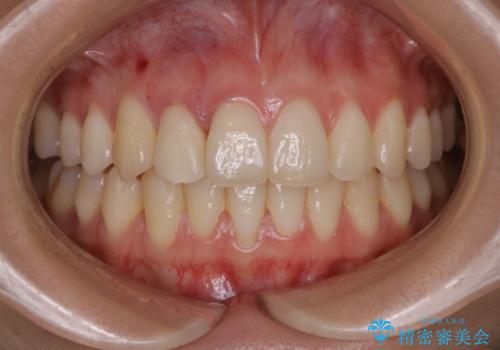

非抜歯でも劇的変化 インビザライン矯正治療

元々の顎骨や口腔・歯槽骨が小さく、どうしても歯が並びきらない状況になっていました。マイクロインプラントという固定源からゴムかけを行うなど、補助装置を活用しながら臼歯部を順番に遠心方向(奥)に移動させていくことで抜歯をしなくても歯が並ぶよう計画を立てました。

歯のガタつきを治すため矯正治療を希望。審査の結果、非抜歯での矯正が可能であるという見通しが立ったためインビザラインによる非抜歯矯正治療を行った。

歯を並べるスペースを作るために、歯の遠心移動と歯列の拡大、歯自体を少しだけ小さく削る(IPR)という方法を複合的に組み合わせて配列を行いました。遠心移動用のゴムかけにはマイクロインプラントという小さいネジを用いて骨に直接固定源を求めました。